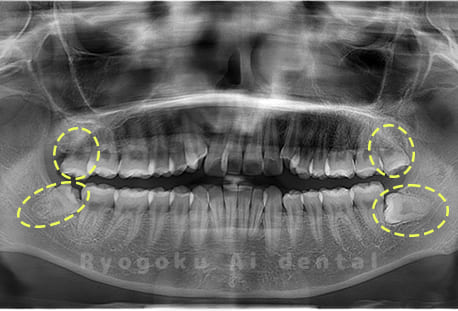

Case01

- 原因

- 水平埋伏智歯

- 治療内容

- 下顎の水平埋伏智歯を抜歯

<リスク・副作用>

手術後は痛み、腫れ、痺れなどの副作用が生じる場合があります。